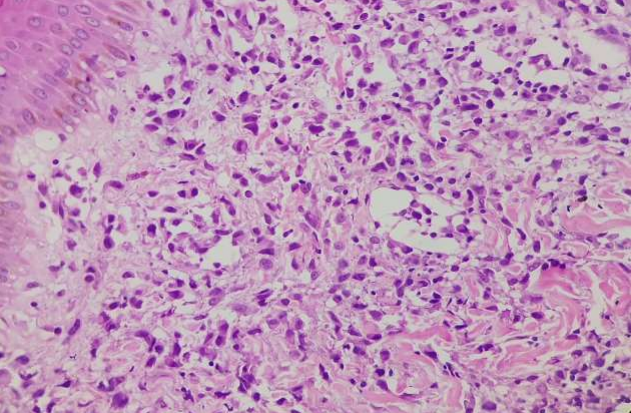

A skin biopsy revealed an interstitial infiltration of atypical cells without epidermotropism in the dermis and subcutaneous tissues. The tumour cells had ill-defined borders, moderate to abundant cytoplasm and oval, elongated or cleaved nuclei with occasional nucleoli with pale to hyperchromatic chromatin. The background consisted of some T cells and scattered small lymphocytes. (Fig 2) Immunohistochemistry, the atypical cells showed positive staining for leukocyte common antigen (LCA), CD30, CD68, and CD4 (Fig   3,4) while negative for CD20, CD45, MPO, CD34, CD117, ALK, PAX-5, AND CK; Ki-67 – 70-80%. (Fig 5) The final diagnoses considered were Lymphamatoid Papulosis Type C or small cell variant of ALCL.[5]A final diagnosis of LyP type C was made based on the waxing and waning course of the disease. Further evaluations including a complete hemogram, chest radiograph, and ultra-sound of the abdomen which did not reveal any abnormality. After careful counselling, patient was asked to be in close observation and steroid cream for local application. Patient was instructed to report she developed any of the following:

Figure 1, 2, 3, 4

Figure 2